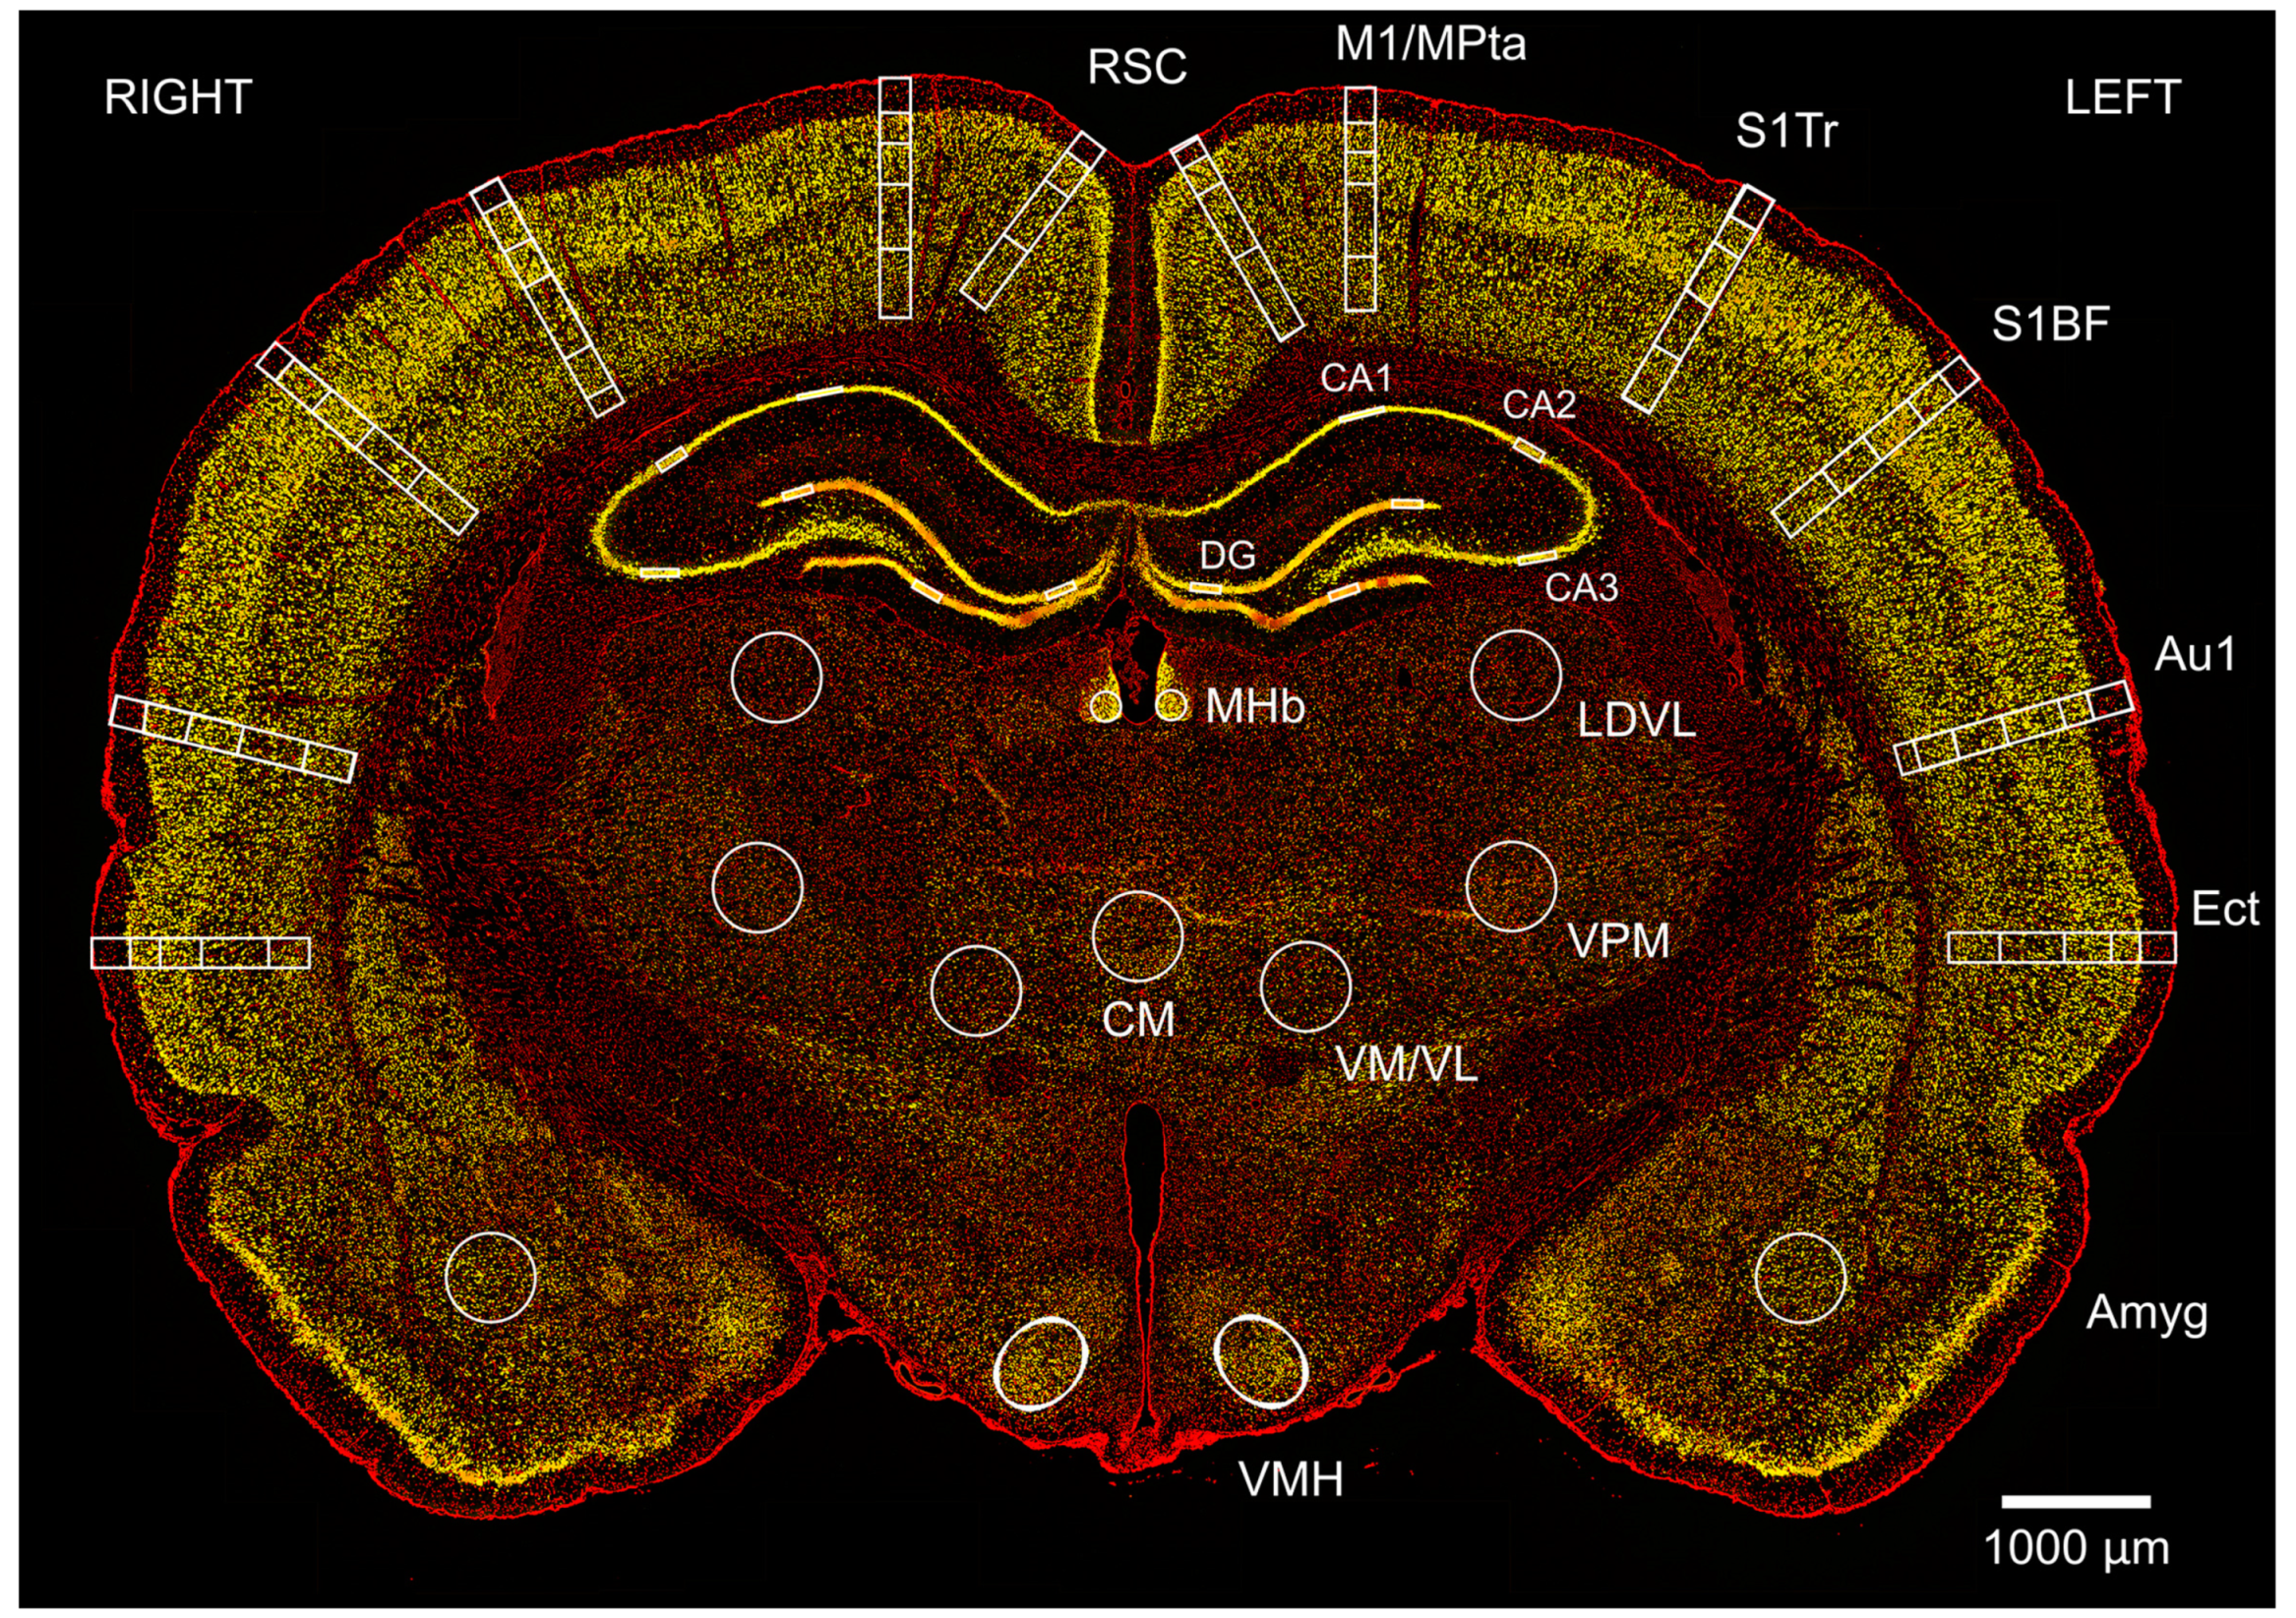

2.10. Histological Processing, Immunofluorescence Staining, Imaging, and Analysis

2.11. Image Analysis

3.8. Exposure to Three Repeated Blast Shockwaves Causes Cortical Neuronal Loss

3.9. Subcortical Regions Are Differentially Sensitive to Three Repeated Blast Shockwaves

4.5. Mapping Neuronal Loss after Repetitive Blast across Cortical and Subcortical Brain Regions